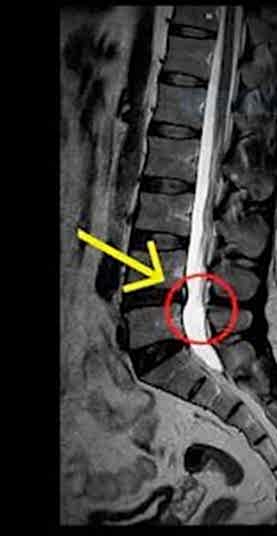

Bel ve boyun fıtığı, omurgadaki disklerin yerinden kayması veya dışarı çıkması sonucu oluşan bir durumdur. Bu diskler, omurlar arasındaki yastıkçıklar olarak görev yapar ve omurga hareketlerini rahatlatır. Ancak, bu disklerin kayması veya patlaması, sinirlere baskı yaparak ağrıya, uyuşma ve kuvvet kaybına neden olabilir.

Bel fıtığı genellikle bel bölgesindeki omurlar arasında meydana gelirken, boyun fıtığı ise boyun omurları arasında oluşur. Bu rahatsızlıkların belirtileri arasında sırt, bel ve boyun ağrıları, bacaklarda uyuşma, kollarda güçsüzlük gibi şikayetler yer alır. Eğer patlamış fıtık tedavisi arıyorsanız, Gaziantep bel fıtığı tedavisi ve boyun fıtığı tedavisi için doğru adrestesiniz.